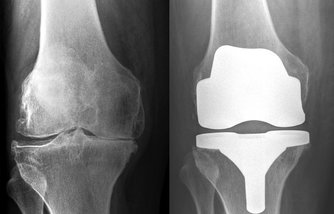

Lůžková část v hlavní budově nemocnice disponuje 28 standardními lůžky a jedním 1lůžkovým klimatizovaným nadstandardním pokojem, lůžková část v "Nové budově" disponuje 9 lůžky a třemi 1lůžkovými klimatizovanými nadstandardními pokoji. 2-3lůžkové pokoje s vlastním sociálním zařízením v moderním designu jsou vybaveny LCD televizí. Za rok provedou ortopedičtí lékaři celkem 1700 operačních výkonů, z toho 650 totálních endoprotetických náhrad kolenních, kyčelních, ramenních a hlezenních kloubů. Současně provádí i revizní operace u pacientů, u kterých došlo v důsledku času k opotřebení nebo uvolnění těchto náhrad. Další významnou skupinou operací jsou artroskopické výkony od prosté diagnostické artroskopie, nanoskopie až po složité rekonstrukční operace kolenního a ramenního kloubu, včetně provádění plastik zkřížených vazů. Dále oddělení provádí ortopedickou operativu v celém rozsahu od rekonstrukcí deformit nohy a přednoží, přes ošetřování entezopatií, řešení osových deformit a následků úrazů. V posledních letech se rozvíjí takzvaná chirurgie ruky, včetně endoprotetických náhrad zápěstí a drobných kloubů ruky.